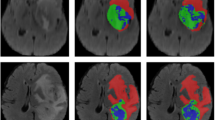

Figure 6 presents some representative visualization results of medical image segmentation using FE-SwinUper. In the figure, yellow areas represent the liver, green areas the spleen, blue areas the right kidney, and cyan areas the left kidney. The first row shows the original abdominal CT images, the second row displays the ground truth segmentation labels, and the third row illustrates the model’s predicted segmentation results. As can be seen, the predicted segmentation results closely align with the ground truth.

Table 1 shows that the proposed FE-SwinUper achieves the best performance metrics among all compared methods, with results of 92.65%, 91.58%, and 12.96, thus verifying the model’s effectiveness. These outcomes validate that the hierarchical feature extraction mechanism based on self-attention and the feature enhancement module in FE-SwinUper significantly improve its multi-scale feature extraction capabilities. Additionally, the adjacent feature fusion module enhances the model’s ability to integrate multi-scale features. The proposed model does not have an advantage in terms of parameter size and inference time due to the additional convolution-based feature enhancement module, which increases the number of parameters. Moreover, the adaptive fusion module incurs significant computational cost during inference. However, considering the performance improvements achieved, these trade-offs are acceptable. Figure 7 presents the visualization results of organ segmentation on abdominal CT images for different comparison models. From left to right are: the original MRI images, the ground-truth segmentation, the segmentation result of the FE-SwinUper model, the result of the ResNet50+DeepLabV3+ model, the result of the ViT+UPerNet model, and the result of the TransUNet model.

Figure 7 demonstrates that the proposed FE-SwinUper model produces segmentation results more closely aligned with the ground truth. It accurately captures all segmentation targets and yields clearer, smoother boundaries. In contrast, the purely convolution-based ResNet50+ DeepLabV3+ approach shows instances of both under-segmentation and mis-segmentation, particularly for smaller organs such as the kidneys and spleen. Compared to other self-attention-based models like ViT+UPerNet and TransUNet, FE-SwinUper achieves better segmentation performance for smaller kidney organs that heavily overlap with the liver, resulting in smoother segmentation boundaries and showcasing superior robustness.